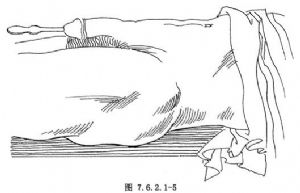

12.4 4.探子尖端進入膀胱

探子尖端通過膜部尿道之後,再將探子向前推進,並邊推進邊將其由與腹壁呈垂直位下壓使之呈平行位(圖7.6.2.1-4)。當完全呈平行位時,探子前部即已進入膀胱,從而完成了整個尿道擴張術的操作(圖7.6.2.1-5)。當探子進入膀胱後即可在尿道及膀胱中左右擰動。尿道擴張術完成後,按上述操作步驟以相反的程序拔出探子。